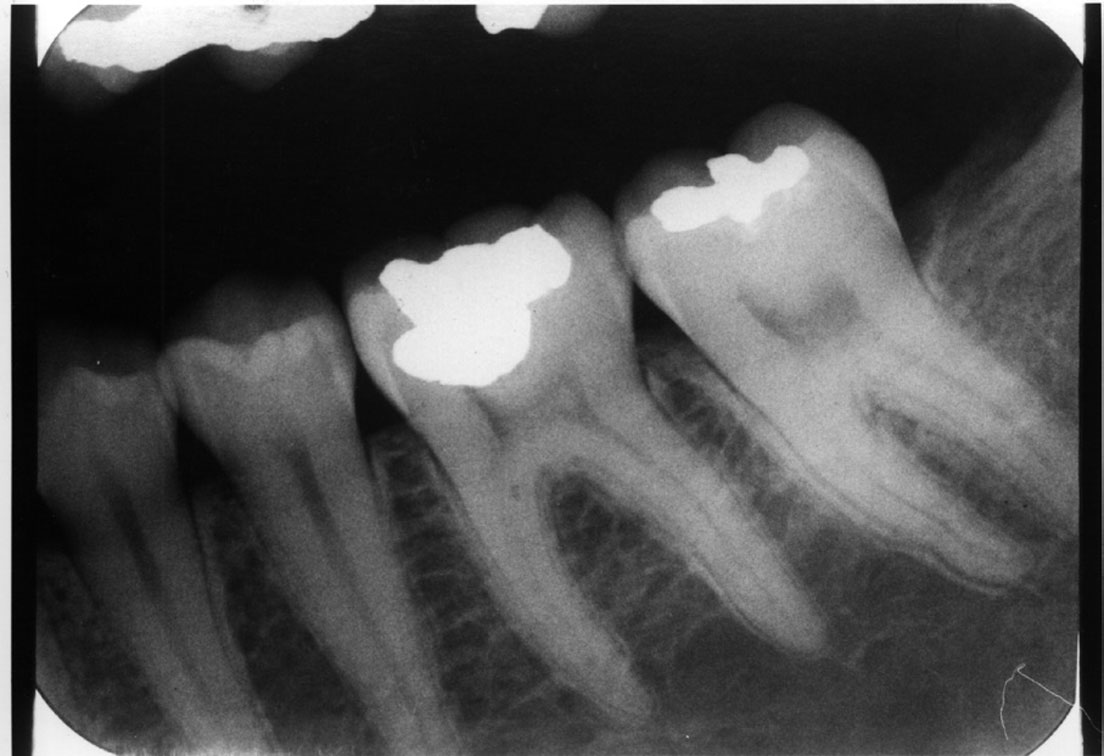

Common Errors In Dental Radiography . Recognize items needing to be removed. It is important for the clinician to be able to understand errors when they occur and how to correct them. Incorrect exposure can be caused by many factors; Define the key terms associated with exposure and technique errors. The most common being improper exposure settings. The focal plane (image layer) in panoramic radiography has limited dimensions; This typically occurs in molar projections when the patient has difficulty. Identify and describe the appearance of the following exposure errors:. Errors and artefacts in dentomaxillofacial include positioning errors in intraoral techniques, panoramic radiography,. Know how to correct intraoral technique errors. A common receptor placement error is inadequate coverage of the area to be examined radiographically. Therefore, minor positioning errors can cause. Table 5 lists various errors that can occur with panoramic imaging.